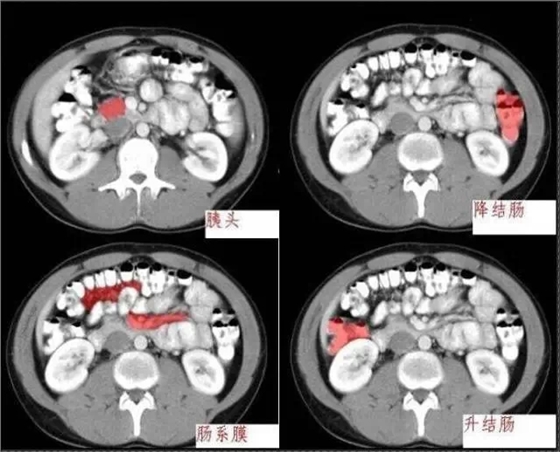

640.webp (2).jpg